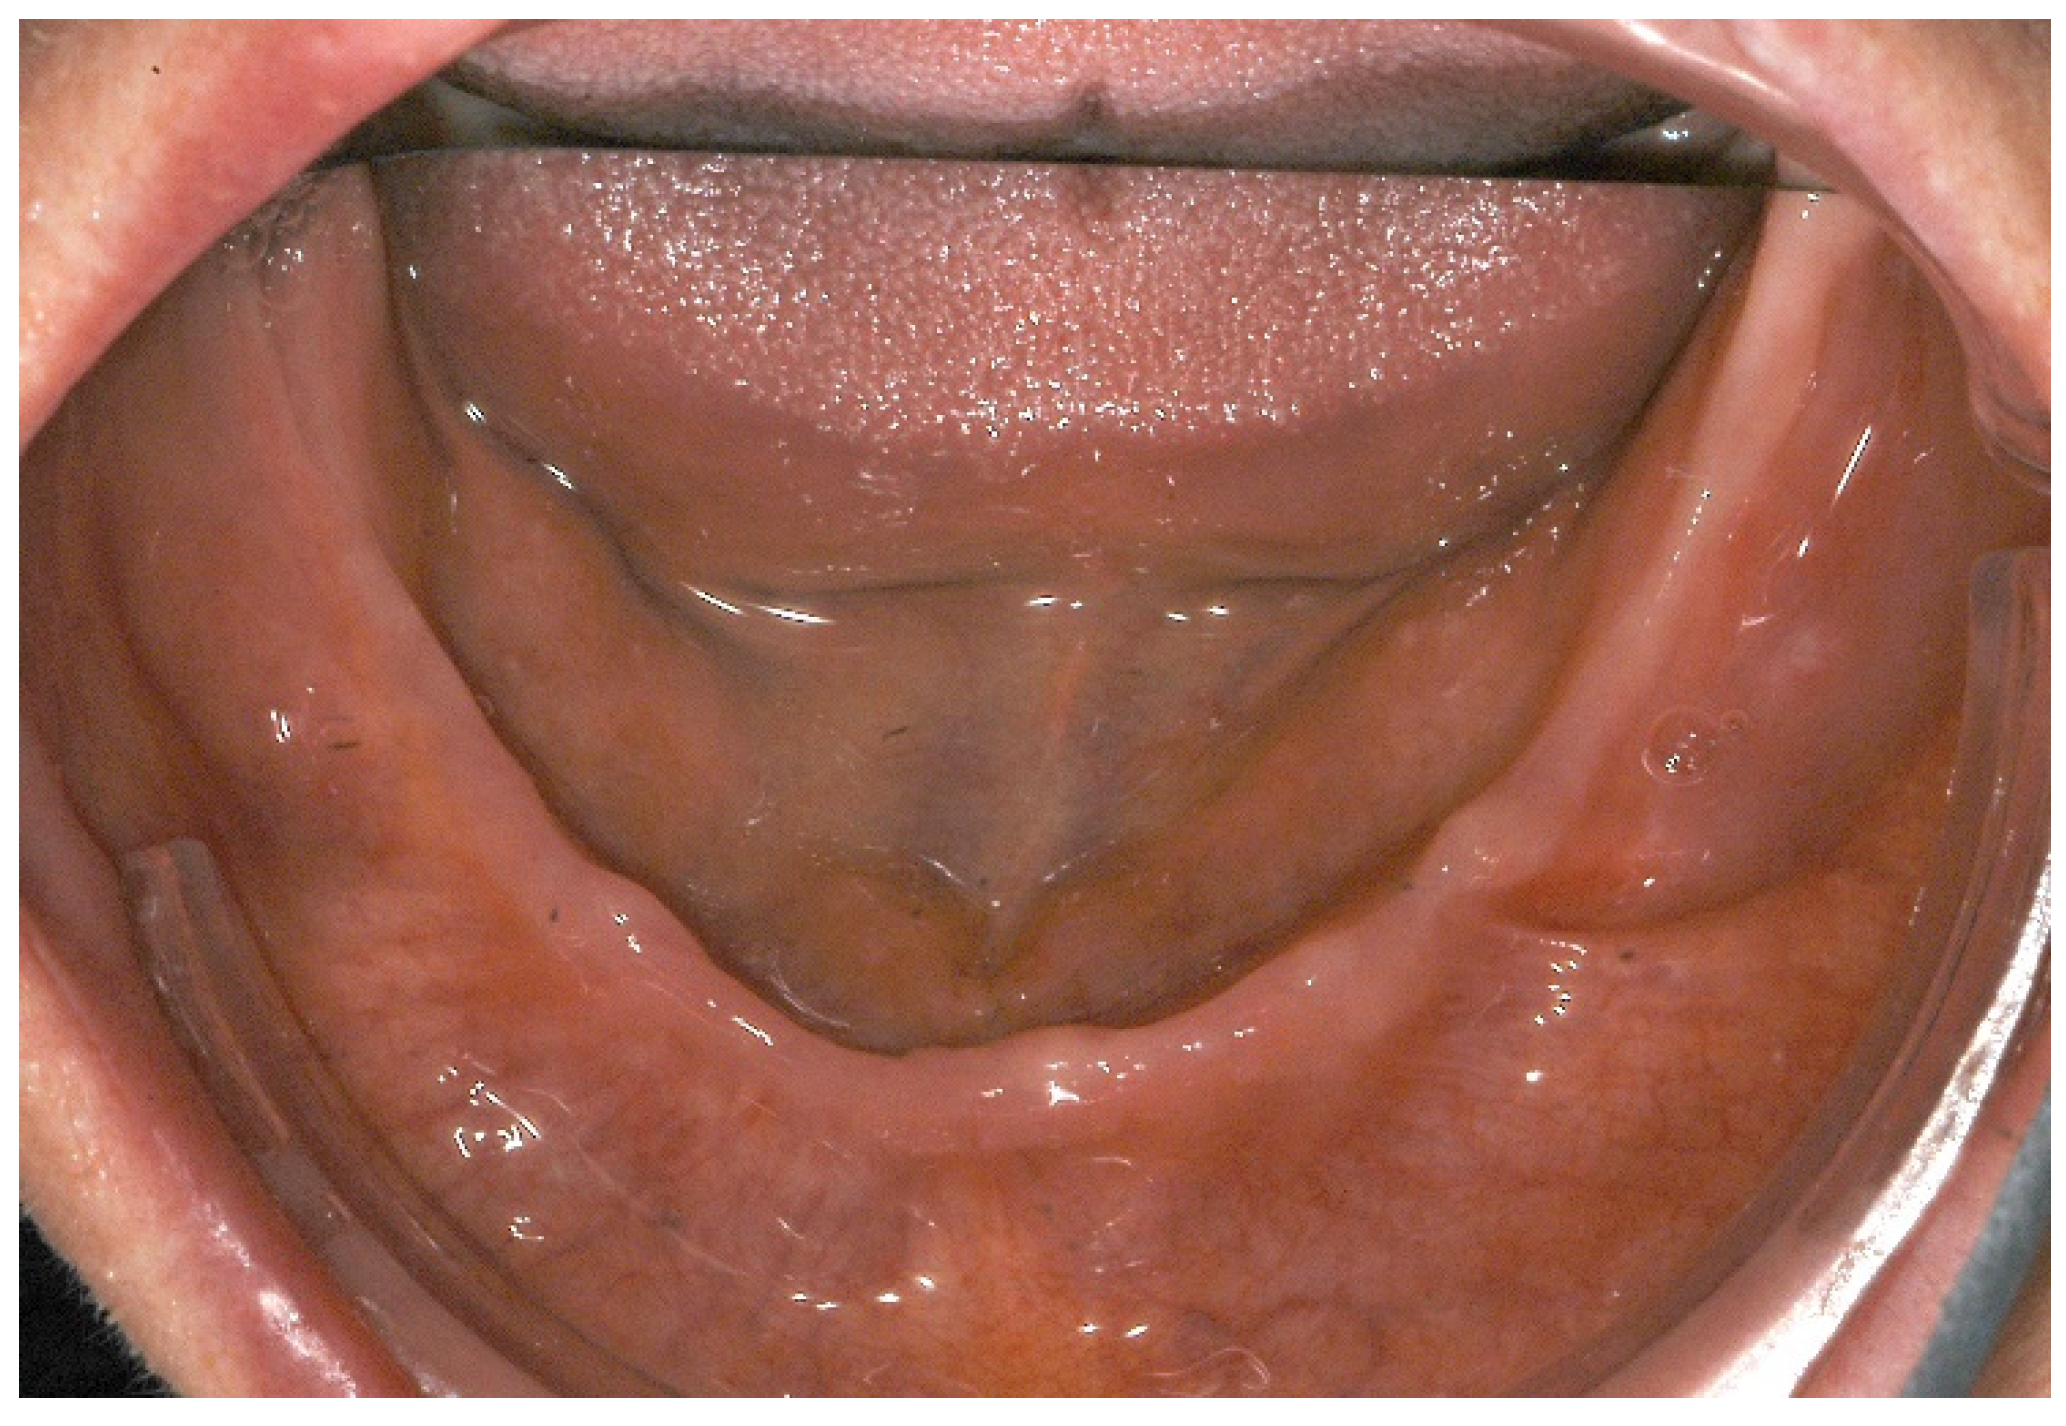

2. Case Report